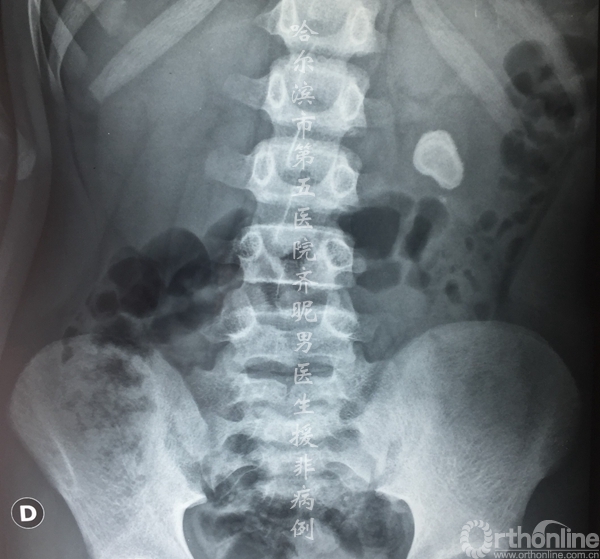

常年喝这样的水带来的结果就是很多人都有泌尿系结石,包括我们医疗队员也有。

这是一个12岁的男孩,在他的左肾里取出了一个直径1.5cm的结石。

是不是比三聚氰胺都厉害?